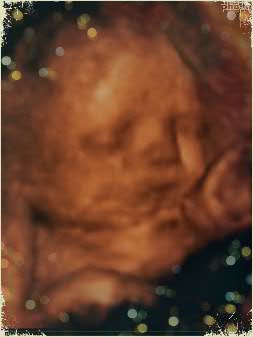

Наше третье плановое УЗИ в 32.1

УЗИ, КТГ, доплерСегодня был очень важный и волнительный день!

Наше последнее плановое УЗИ.

Мы,еще раз,увидели нашего славного и самого красивого мальчика - Платошу!

Наш сладкий,маленький Комочек по размерам соответствует 34 неделям.

Да,нам поставили тенденцию к крупному плоду.

Вес приблизительно 2.400(+/-340 гр).

Плацента по передней стенки матки на 7 см выше внутреннего зева.Толщина плаценты нормальная до 33 мм,структура однородная.Степень зрелости 1.

Количество околоплодных вод:норма,без взвеси.

Пупавина имеет 3 сосуда.

Так же показал,что яички уже опустились и писюнок имеет правильное строение))

Окружность головы 308 мм

Окружность животика 309 мм

Длинна бедренной кости 66 мм(левой и правой)

Серцебиение ясное,ритмичное,до 136 уд./мин.

Лежит головкой вниз)